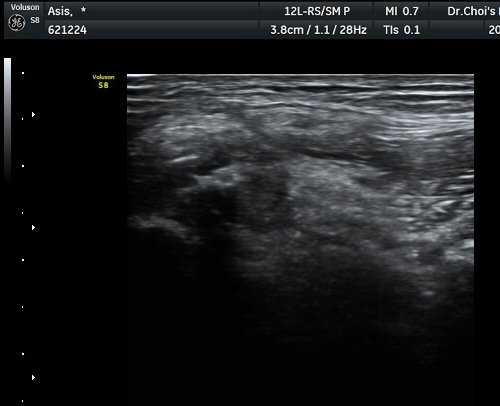

°üÂûµÇ°í(±×¸² 1) ¿ÜÃø´ëÅð±ÙÇǽŰæÀÇ ºÎÁ¾ÀÌ °üÂûµÊ(±×¸² 2, 3). Àü»óÀå°ñ±Ø Ⱦ´Ü¸é°Ë»ç¿¡¼­

°ß¿­°ñÀýµÈ °ñÆí°ú ¿ÜÃø´ëÅð±ÙÇÇ½Å°æ ºÎÁ¾ÀÌ °üÂûµÊ(±×¸² 4).